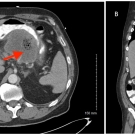

A 27-year-old man presented to the emergency department (ED) following a new-onset seizure. The seizure was witnessed by his wife, who stated that he was standing at the kitchen sink, washing dishes, when...